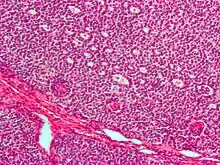

Micrograph of a granulosa cell tumour, a type of sex-cord–gonadal stromal tumour. H&E stain.